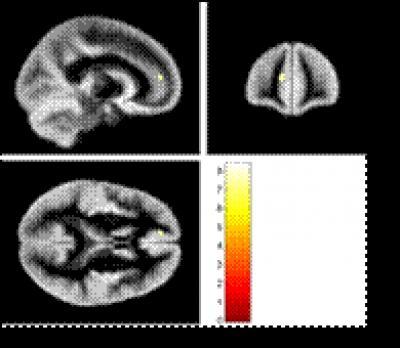

Voxel-based morphometric analysis showed that the volume of the gray matter in the cingulate of the dominant hemisphere in relapsing-remitting multiple sclerosis patients was significantly reduced.

(Photo Credit: Neural Regeneration Research)